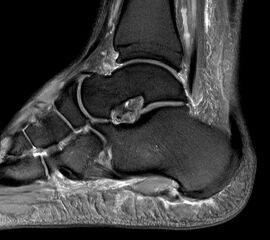

Abbildung 6: Darstellung des Baxter Nerven im MRT (siehe Pfeil)

Zum Lesen der Bildbeschreibung und zur Vollansicht bitte das Bild anklicken. Bild: Manfred Thomas.

Abb. 9a–d: chron. Plantarfasziitis mit plantarem Fersensporn und Irritation Baxternerv plantar lateral

Kasuistik: 28-jähriger Patient, Profisportler.

Abb. 9a: Plantarer Fersensporn und Plantarfasziitis im MRT prä-op.

Abb. 9b: Plantarer Fersensporn im CT prä-op.

Abb. 9c: Lateraler Zugangsweg bei atypisch weit nach plantar lateral liegendem Sporn.

Abb. 9d: Röntgenkontrolle nach Minioffenem Plantarfaszienrelease und Abtragung Fersensporn mit Neurolyse.

Zum Lesen der Bildbeschreibung und zur Vollansicht bitte die Bilder anklicken. Bilder: Manfred Thomas.